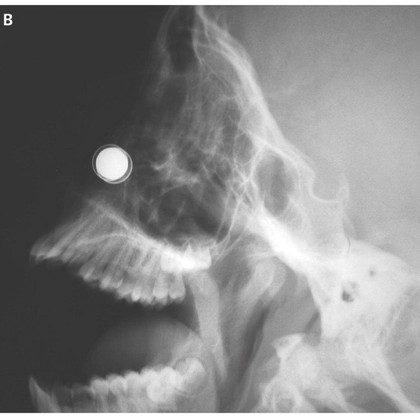

Ketika sudah di dalam tak sengaja magnet tersebut menarik satu sama lain dan tersangkut. Sang anak tidak bisa mengeluarkannya lagi, kesakitan, dan setelah enam jam hidungnya mulai berdarah. Hasil rontgen menunjukkan bahwa magnet menjepit bagian dinding hidung yang memisahkan lubang hidung kiri dengan kanan. Awalnya dokter mencoba memisahkan kedua magnet tersebut dari luar namun gagal. “Upaya untuk mengeluarkan magnet di ruang gawat darurat gagal karena saking kuat daya tariknya,” tulis dokter seperti dikutip dari Live Science, Sabtu (28/10/2017).